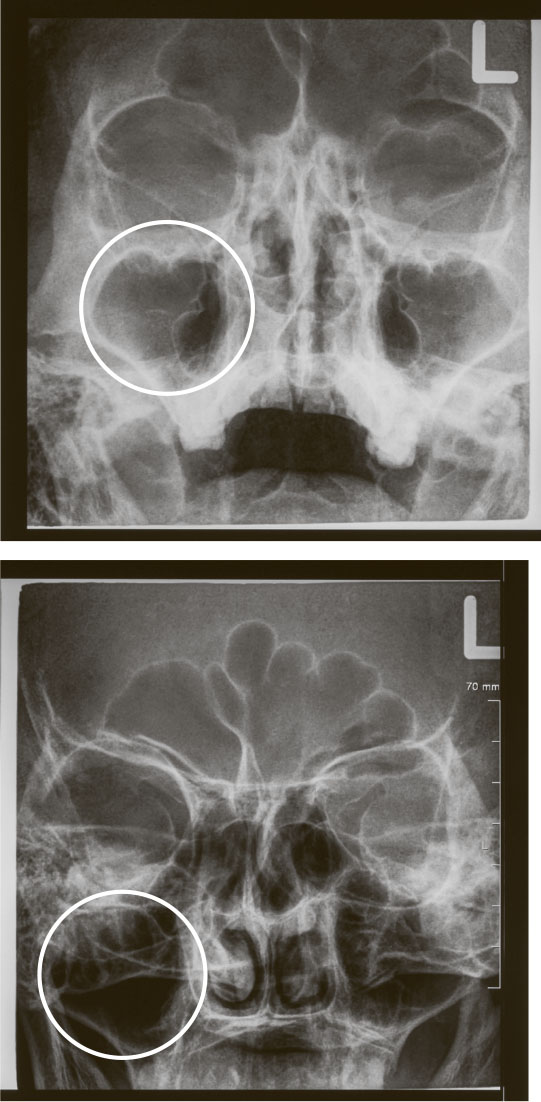

РЕНТГЕН ПАЗУХ (РЕНТГЕНОГРАФИЯ ЧЕРЕПА В НОСОЛОБНОЙ И НОСОПОДБОРОДОЧНОЙ ПРОЕКЦИИ)

Практически полностью утратил актуальность. Для диагностики острого воспаления (гайморитов, фронтитов) не применяется (см. рекомендации AAO-HNS, EPOS-2020, ICAR: rhinosinusitis 2018, рекомендации Российского общества ринологов 2019). Данный диагноз ставится клинически: по симптомам, анамнезу и картине при осмотре. Для диагностики хронических проблем в пазухах совершенно бесполезен.

В чем суть? На рентгенограмме (снимке) можно было увидеть отек слизистой оболочки или наличие жидкостного содержимого в пазухе. Проблема в том, что изображение получается двухмерное, и, например, если отек затрагивает переднюю стенку пазухи – ту, что расположена вертикально под глазом, – и он достаточно плотный, на рентгенограмме может показаться, что вся пазуха заполнена, допустим, гноем. И это приводило к довольно суровым последствиям, учитывая карательный дух отечественной медицины.

Кроме того, рентгенография не визуализирует в достаточной мере решетчатый лабиринт, а клиновидную пазуху не захватывает вовсе.

Накидываем дальше. При любом насморке рентгенограмма может демонстрировать затемнение в пазухах, и это тоже благополучно интерпретируется как призыв к агрессивной терапии, когда в действительности в том нет никакой необходимости.

Нокдаун – при каком-либо хроническом процессе на рентгеновском снимке нельзя увидеть важных структур, позволяющих принять решение о хирургическом вмешательстве.

И К.О.: рентген пазух абсолютно бесполезен при заболеваниях полости носа у детей из-за упомянутых выше особенностей анатомии. У части здоровых детей на рентгенограмме в норме визуализируется затемнение пазух. Если обследуют ребенка с насморком, затемнение может определяться везде в силу того, что слизистая носа, как мы говорили, очень чувствительна к воспалению. Нерадивые рентгенологи даже отсутствие пазухи (а это ситуация нередкая, ведь они развиваются довольно рандомно) могут расценить как тотальное затемнение, то есть посчитать, что пазуха заполнена гноем.

Рентгенограмма черепа в носоподбородочной (сверху) и носолобной (снизу) проекции. Имеется затемнение правой гайморовой пазухи (она светлее, чем левая – да, в рентгенологии все наоборот)

Ваш покорный слуга неоднократно имел дело с детьми, стоически переносящими второй-третий курс антибиотиков (нередко уже внутримышечных), в целях лечения мифического фронтита (воспаления в лобных пазухах). Правда, был один нюанс: лобных пазух у этих ребят не было в принципе. Родители, обнаружив сей факт, испытали значительный когнитивный диссонанс.